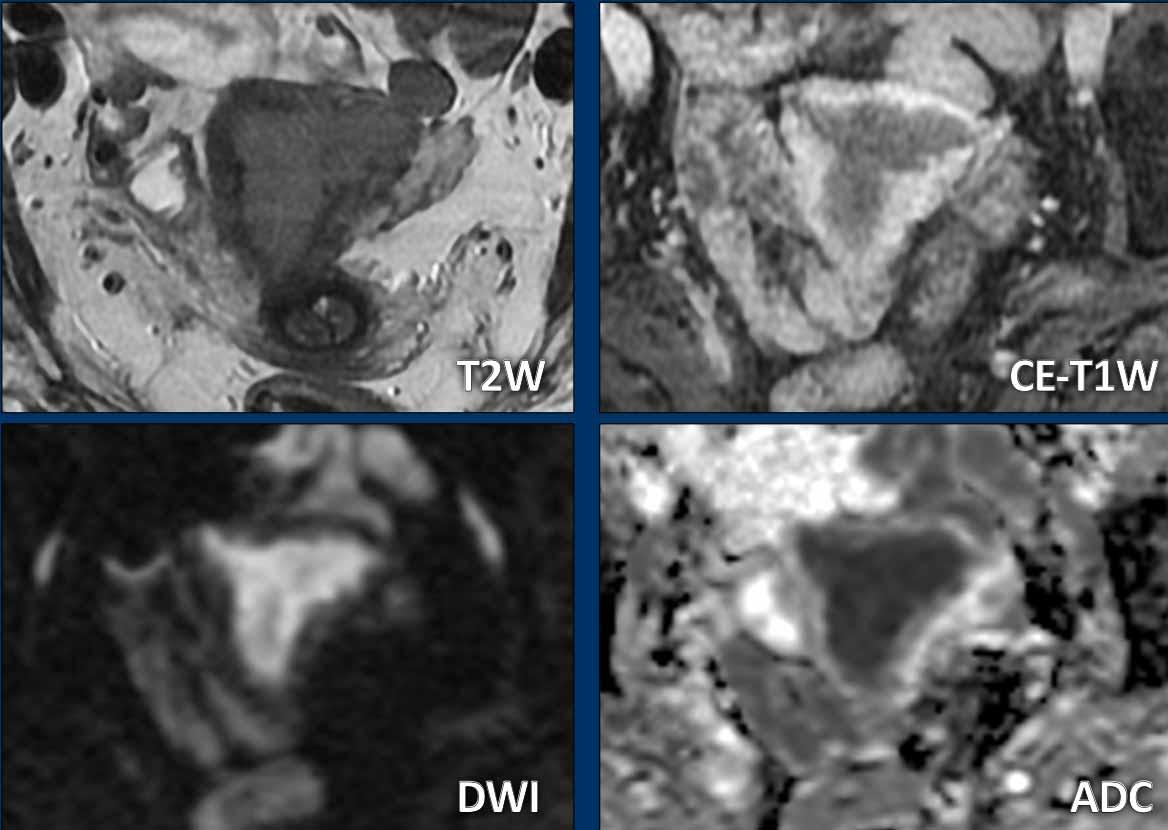

Đôi khi các khối u kém rõ và khó xác định ranh giới trên chuỗi xung T2W.

Trong những trường hợp như vậy, chuỗi xung DWI (và bản đồ ADC) cùng chuỗi xung T1 sau tiêm thuốc tương phản từ có thể giúp xác định ranh giới và đo kích thước khối u tốt hơn.

Hầu hết các ung thư nội mạc tử cung biểu hiện tăng tín hiệu rõ rệt trên DWI với giá trị b cao và kém mạch máu so với cơ tử cung xung quanh trên chuỗi xung T1W sau tiêm thuốc tương phản từ.